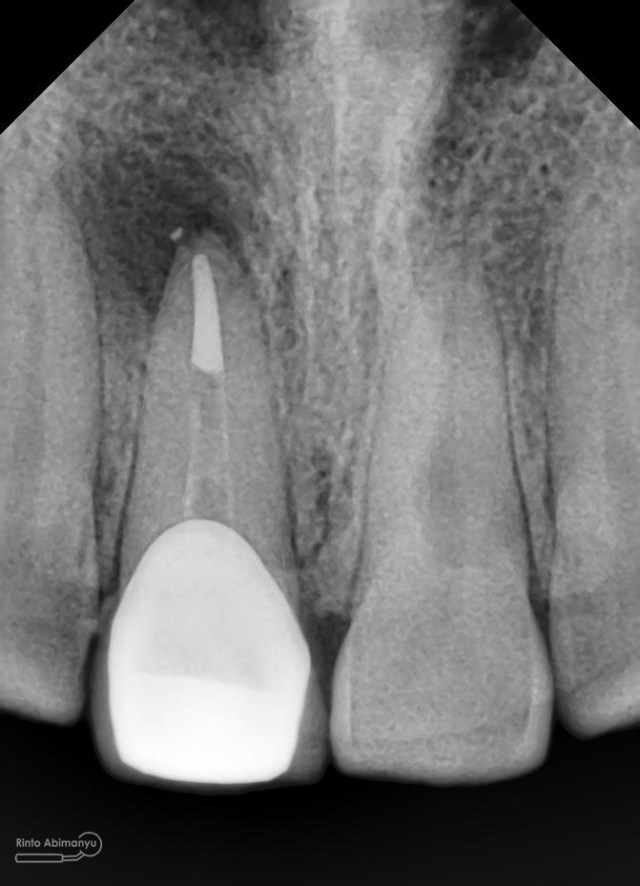

Oo iya tidak lupa juga dilakukan foto ronsen setelah pemasangan crown…

Foto radiografis akhir

Dari foto ronsen terlihat gambaran yang “indah” dari mulai pengisian saluran akar yang rapat dan padat serta gambaran sementasi mahkota yang terlihat homogen….